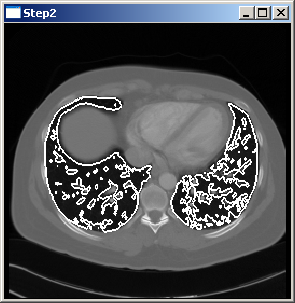

The picture above shows the result of the program when reading both the image file and the surface file.

In order to obtain the result the program has to be executed using the image file mitk/Core/Code/Testing/Data/Pic3D.pic.gz and the surface file mitk/Modules/MITKExt/Testing/Data/lungs.vtk.